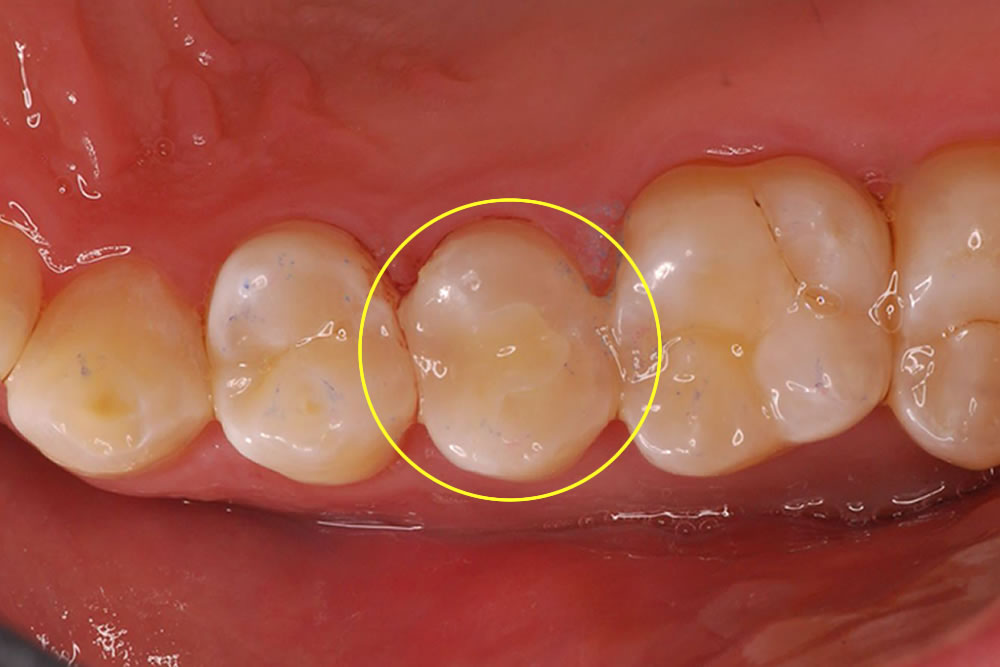

ジルコニアセラミックを用いて銀歯を白い歯にした審美症例

部分的に入った保険の銀歯を外して、ジルコニアセラミックのかぶせ物で見た目を改善した症例をご紹介します。(▼画像はクリックで拡大します)

噛む面と右の側面から見るとこのようになっています。患者さまと相談した結果、こちらの銀歯を取り除き、白い歯(ジルコニアセラミック)を被せて見た目を改善する治療計画を立てました。

| 年齢/性別 | 30代/男性 |

|---|---|

| 治療期間 | 1ヵ月 |

| 治療回数 | 2回 |

| 治療費 | セラミックアンレー143,000円(税込) |

| リスクなど | ・かぶせ物のセラミックが欠けたり、割れる可能性がある。 ・症例によっては歯を多く削る場合がある。 |